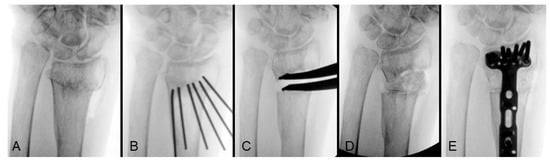

To achieve radius lengthening, simple manual traction as treating acute fracture is generally ineffective, even after extensive soft tissue release. The lengthening should be addressed from the osteotomy site using two primary methods: 1. Applying a distraction force with a lamina spreader to incrementally open the gap. 2. Inserting osteotomes into the osteotomy site and gradually spreading them apart to create and widen the gap. This process is monitored by fluoroscopy to ensure proper alignment and height. Once the appropriate radial height is achieved, the osteotomy gap is filled with bone graft to maintain the correction. Allograft or autograft can be used depending on the availability and the extent of the lengthening required. Figure 1 demonstrates the step-by-step process of the length correction for an extra-articular distal radius malunion (Figure 1A). The osteotomy plane was initially formed by multiple K-wires (Figure 1B), followed by radial height lengthening using a lamina spreader (Figure 1C). The defect further was then filled with allograft (Figure 1D), and definitive fixation was achieved with a volar locking plate (Figure 1E). According to the lengthening technique reported by Huang et al., all 10 enrolled patients achieved bone healing within three months post-surgery. The average lengthened distance (change in ulnar variance) was 5 mm, with a range of 3 to 8.5 mm [31].

Figure 1. Correction of shortening from extra-articular distal radius malunion: (A) preoperative anteroposterior view; (B) osteotomy plane created by multiple K-wires; (C) length corrected with lamina spreader; (D) allograft insertion; (E) definitive fixation with volar locking plate. Image courtesy of the corresponding author Chen-Yuan Yang, MD.